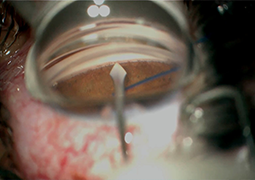

- Outcomes of Chandelier-Assisted Segmental Scleral Buckling Compared to Conventional Scleral Buckling for Primary Rhegmatogenous Retinal Detachment: A comparative retrospective study